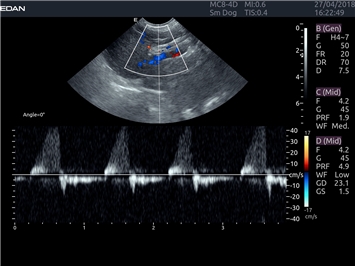

EDAN Acclarix LX4 VET представляет собой профессиональную ультразвуковую систему, специально разработанную для ветеринарных исследований. Сочетание стабильности, высокой производительности и эффективности делает эту систему идеальным выбором для современной ветеринарной практики.

Цветовой допплер:

Да

Постоянно-волновой допплер:

Импульсно-волновой допплер:

Дуплексное сканирование: